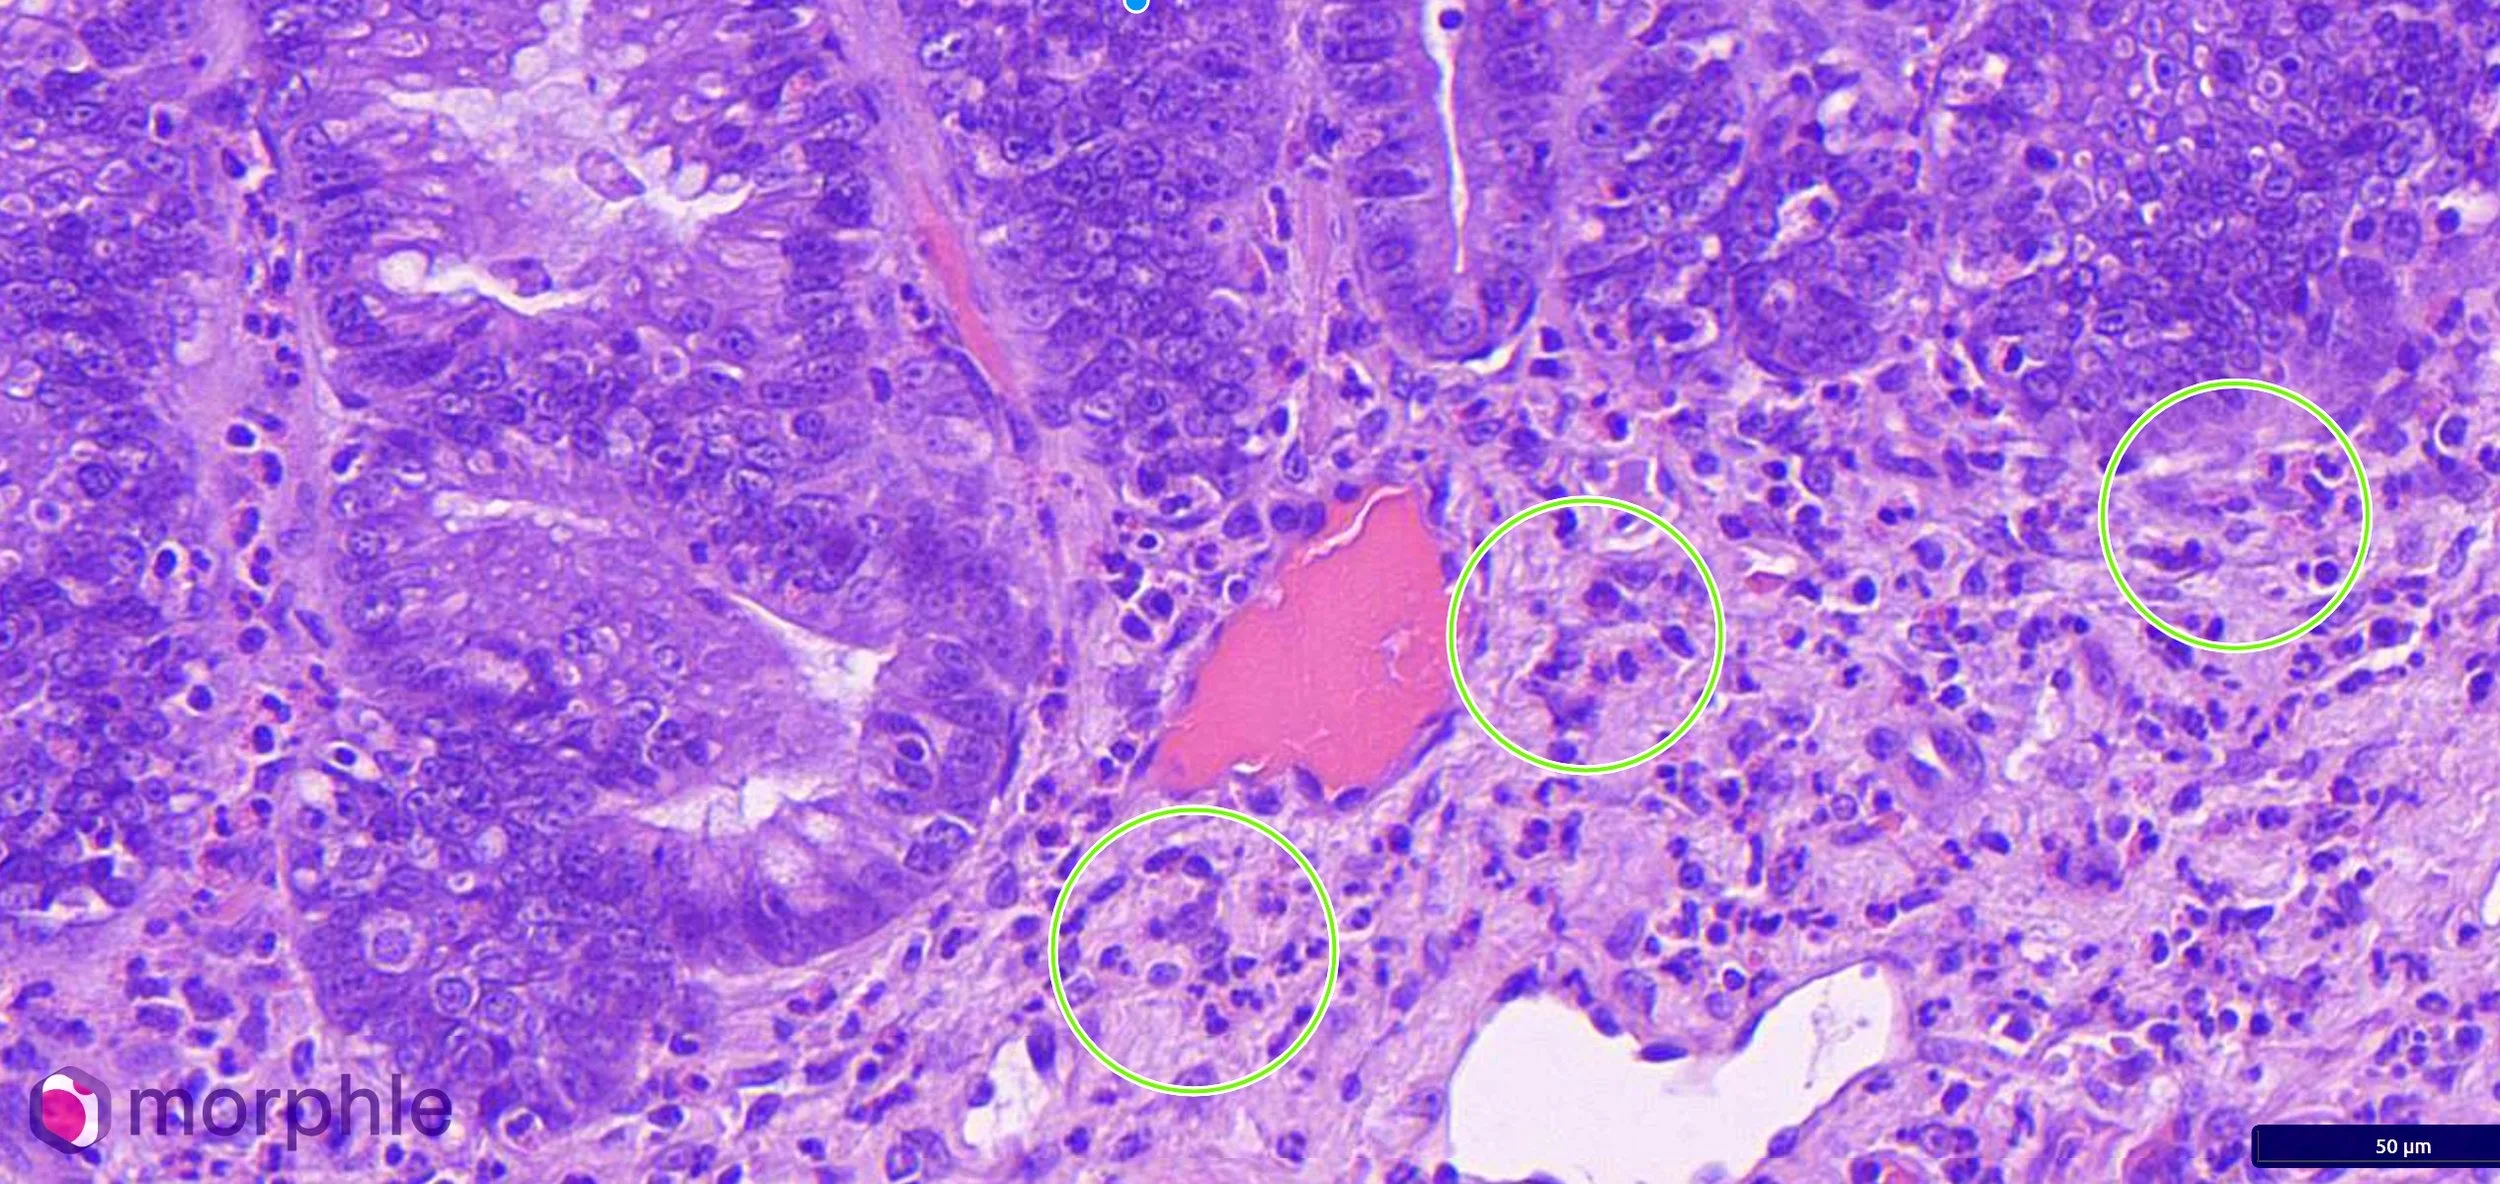

Sections of small intestinal wall revealed a marked eosinophilic infiltrate throughout the lamina propria. Eosinophils were present in high numbers in all sections examined, with infiltration extending into the crypts and disrupting the normal crypt architecture in areas. Villous blunting and crypt irregularity were present, consistent with chronic mucosal injury. The degree of eosinophilic infiltration was inconsistent with a reactive response to the foreign body alone — the distribution and severity indicated a pre-existing, active inflammatory process.

Histopathology of enteritis. The circles are representative areas with eosinophils present. Eosinophils are present in much higher numbers than typically expected in the instestine.